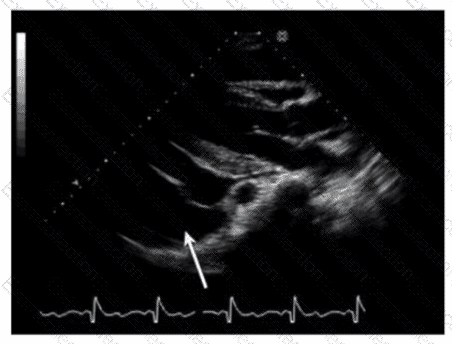

Which finding is indicated by the arrow on this image?